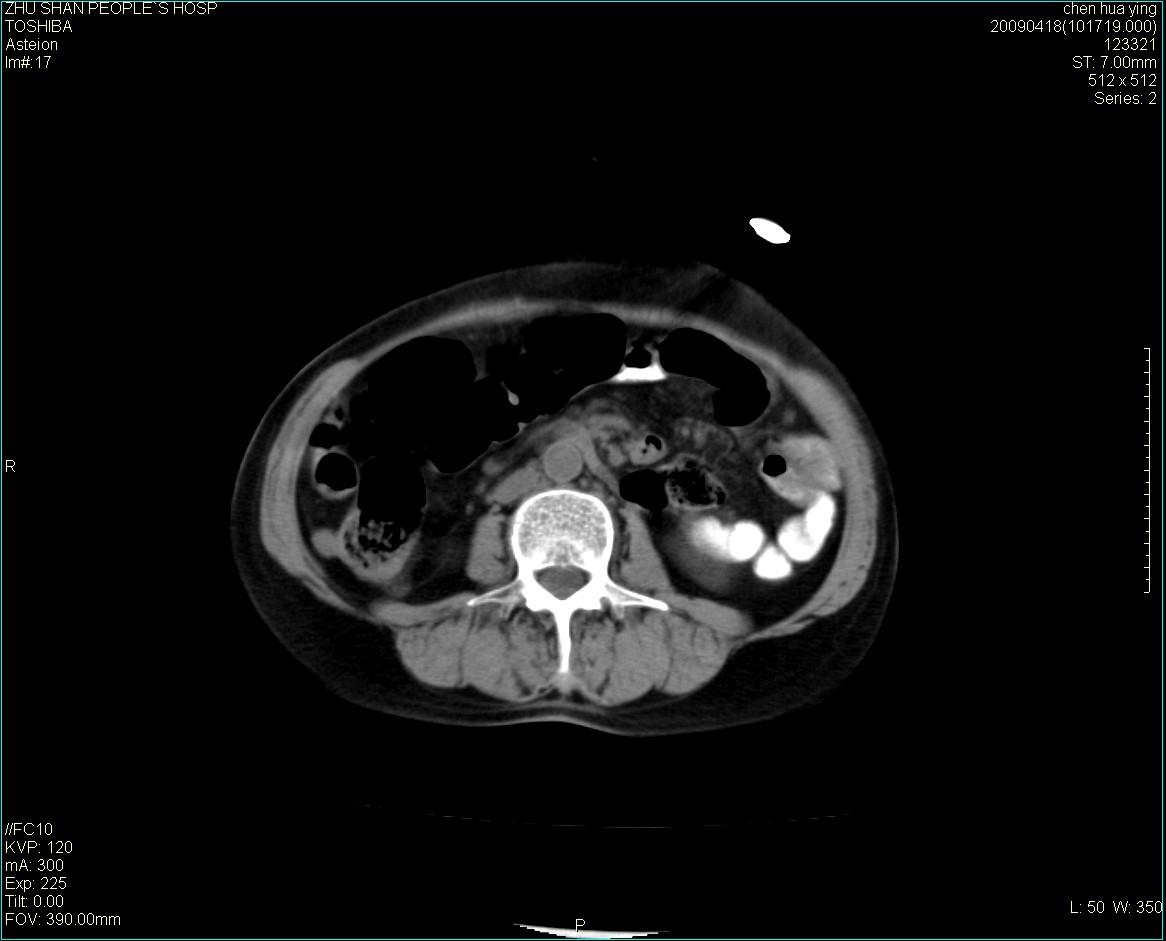

女性病人 65岁 腹部包块半年余结肠造影未见异常.

病灶略呈圆形有分叶状,上部层面呈实性,右侧见圆形低密度区,灶内见团块状钙化,病灶下方与肠管分境不清,考虑间质瘤可能性大,建议肠道准备后增强